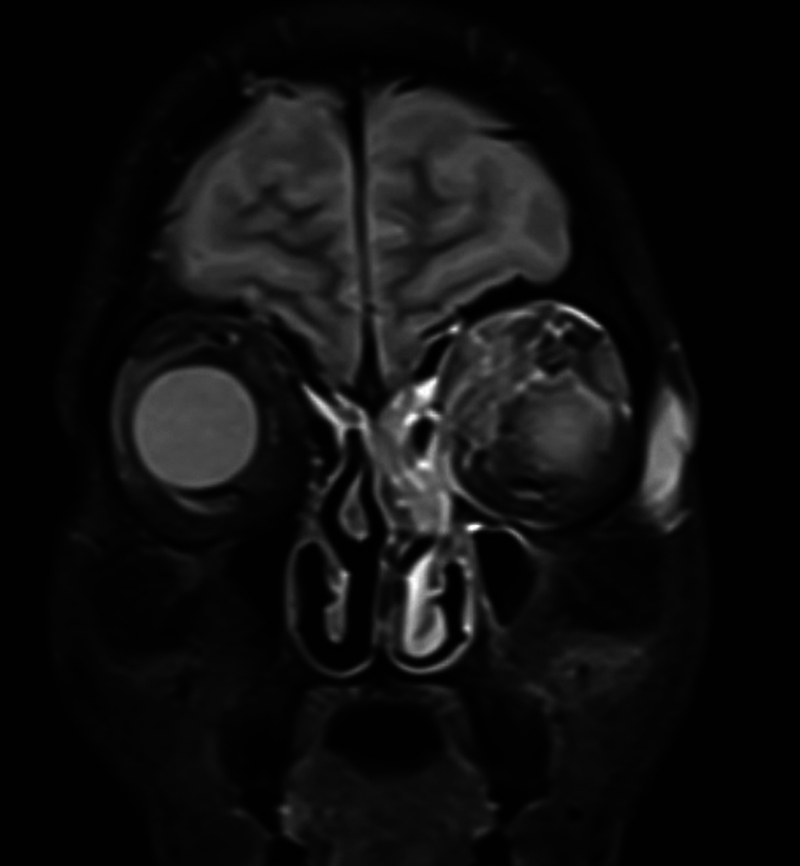

Introduction  Mucormycosis is an aggressive, lethal fungal infection affecting the nasal and paranasal territory in immunocompromised patients. Orbital involvement is not uncommon and may require orbital exenteration. Objectives  The management of orbital involvement in invasive fungal sinusitis is challenging, ranging from conservative retrobulbar amphotericin B injection in the early stages to orbital exenteration in late stages. Endoscopic endonasal debridement is a minimally invasive technique used to manage orbital fungal involvement in the late stages. Methods  Endoscopic endonasal orbital clearance was performed to manage late-stage orbital invasive fungal infection (≥ stage 3c) or after failure of retrobulbar amphotericin B injection with no light perception. Removal of the lamina papyracea (LP) and incision of the periorbita were done to expose all the necrotic intraorbital content in the extra and intraconal spaces. A microdebrider was utilized to debride necrotic fungal infected tissue until a healthy vascularized plane was reached. Gelfoam (Pfizer Inc., New York, NY, United States) soaked in amphotericin B was applied as an adjunctive step to deliver antifungal medication to the orbital content. Results  Fourteen patients were included in the study, 9 of whom were male and 5 female, with a mean age of 58.5 years. Eleven patients showed no evidence of disease progression (complete recovery and cessation of medical treatment). Two patients died 15 days after the surgery. The last patient developed frontal lobe abscess but has been treated with double antifungal medication. Conclusion  Endoscopic endonasal orbital debridement could be an effective method to treat late-stage orbital fungal infection without jeopardizing the patient's life. Level of Evidence : 4.